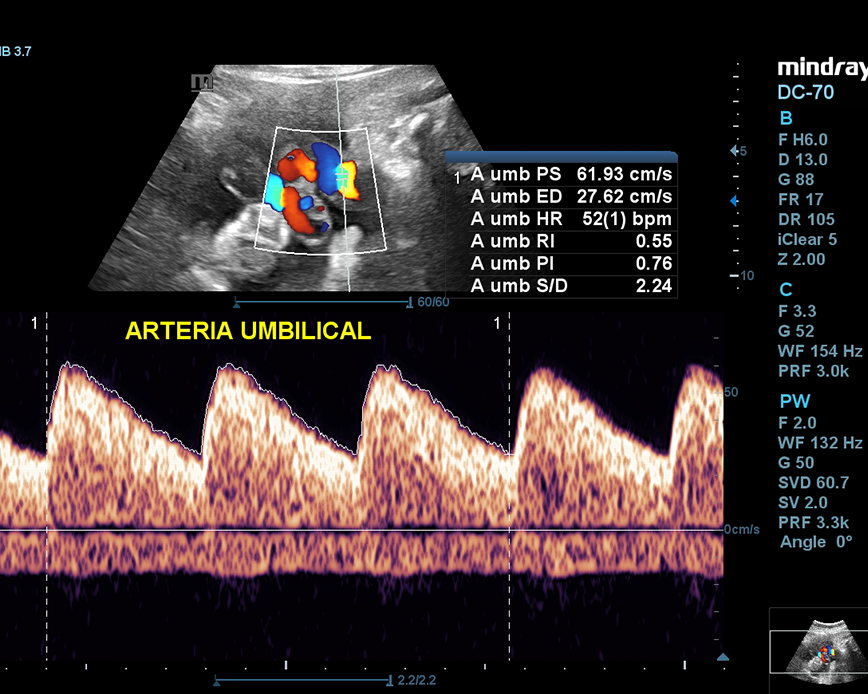

Esta ecografía sirve para evaluar la hemodinamia materno-fetal y detectar problemas de crecimiento como el RCIU (Restricción del Crecimiento Intrauterino) y el riesgo de preeclampsia (presión arterial alta durante el embarazo). Además, nos permite evaluar el cordón umbilical y detectar circulares de cordón simple, doble o triple.